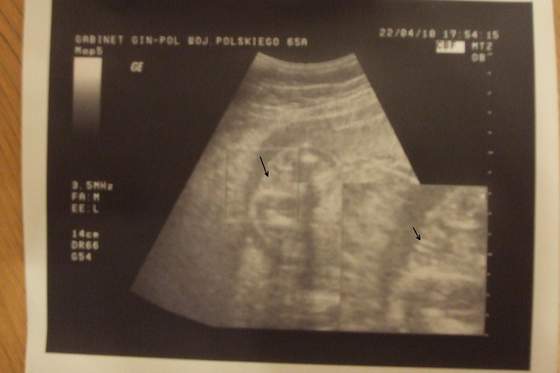

Mój mały uparciuszekZdjęcie zrobione z filmiku 4D. Dowodu męskości nie wstawiam, zaręczam że jest.